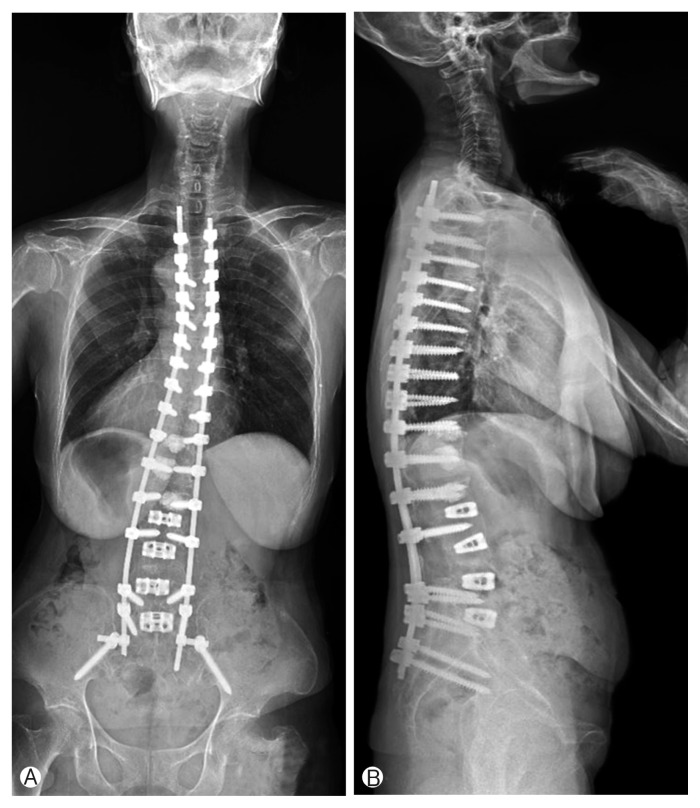

The initial L5-T12 in green posterior fixation turned into S1-T9 in green + yellow + blue for an osteoporotic patient.

In green is what we would give for 100% of the patients as a first procedure: 78% will have a satisfactity clinical outcome.

But 22% of the osteopenic/osteoporotic patients will suffer from BMD related complication with this limited montage.

In blue and yellow: vertebral extention required for the 22% to avoid BMD related complication. Yellow indicates selective pedicle augmentation.